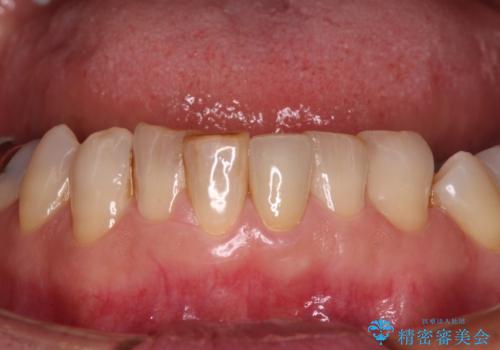

- 下顎前歯が痛んで近医を受診したところ、下顎前歯2本を抜歯してインプラント治療が必要と診断されたとのことで来院された患者様です。

診査の結果、下顎左側中切歯の神経が失活していることが痛みの原因であり、根管治療を行う必要があると診断されました。

根管治療を行った後にオールセラミッククラウンにて補綴することとしました。

隣在歯にも根尖部の炎症が及んでいるように見えましたが、術前診査では神経が失活している様子がなかったため、まずは原因歯から処置を行うこととしました。

初回の根管治療後には痛みが速やかに改善し、6か月後のレントゲン写真では根尖の病変が消失していることが確認できました。